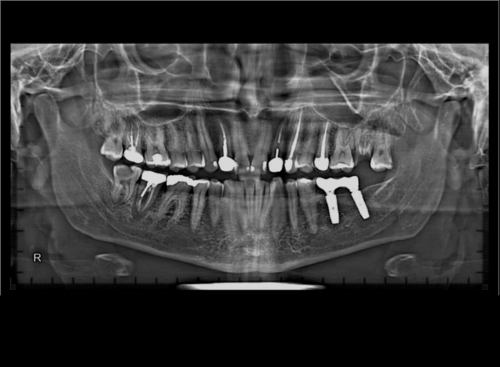

Fixed partial dentures are a permanent solution to replace missing teeth, offering the look, feel, and function of natural teeth. Unlike removable dentures, they are securely attached using dental implants or tooth, so you can eat, speak, and smile with confidence — no slipping or clicking.

These dentures restore your bite strength, improve facial appearance, and are custom-designed to fit comfortably in your mouth. They’re ideal for patients seeking long-term comfort, stability, and a natural-looking smile.